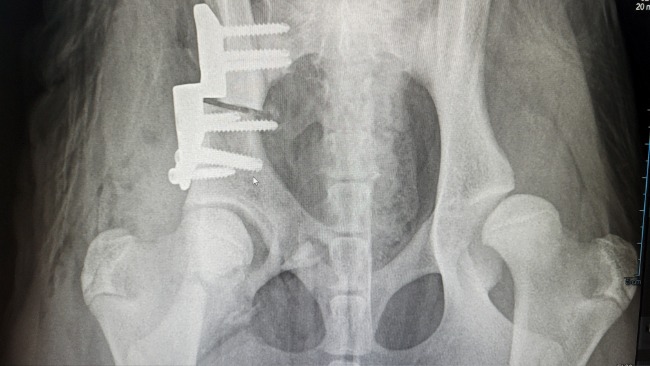

Zachowanie Kokosa nas niepokoiło, było czuć pod dłonią w miejscu opweiwwnym że coś się porusza. Szybkie RTG - złamanie główki kości udowej.. Z niczyjej winy - ryzyko, powikłanie po zabiegu 😭 (miejsce gdzie widoczna jest myszka komputerowa).

Kokos został w szpitalu i miał kolejny zabieg aby złączyć te kości i ostatecznie ma kolejną ranę oraz gips.. Porusza się na 3 łapach, gips uciska mu cewkę moczową co utrudnia oddawanie moczu..